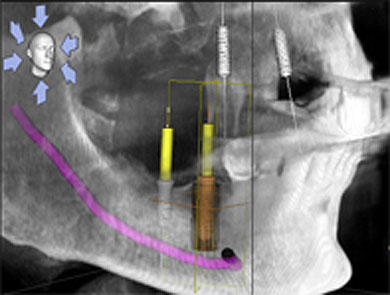

3-D navigierte Implantation

Mit unserem speziellen Planungssystem können wir schon vor einem Eingriff feststellen, wieviel Knochen zur Verfügung steht. Anschließend planen wir virtuell die richtige Position der Implantate.